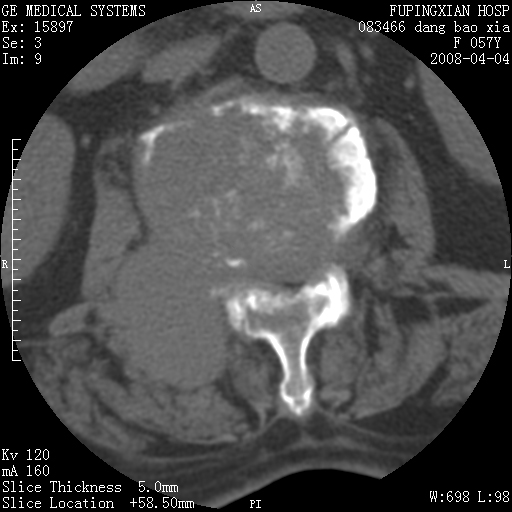

标题: CT12677:女性,57岁,疼痛数月。 [打印本页]

标题: CT12677:女性,57岁,疼痛数月。

椎体及附件骨质破坏同时伴软组织肿块,首先考虑恶性肿瘤。

椎体及附件骨质破坏,伴软组织肿块,首先考虑恶性骨肿瘤,建议提供正侧位片。

骨组织起源,膨胀,软组织肿块=恶性改变:首选骨巨,其次转移瘤,再次脊索瘤

椎体及附件溶骨性破坏,周围巨大软组织肿块,首先考虑转移瘤。